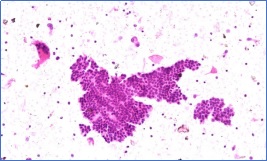

甲状腺乳头状癌FNAc液基细胞学标本(常规HE染色)